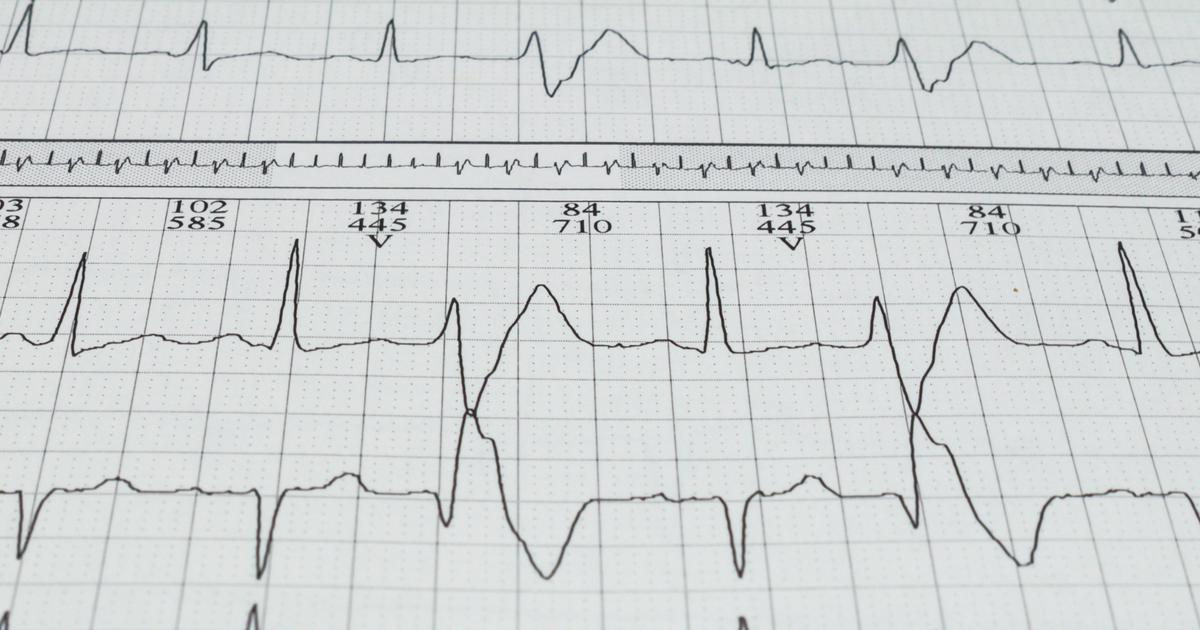

Irregular Heartbeat

An individual who experiences an irregular heartbeat with other muscle-related symptoms may be affected by rhabdomyolysis. The heartbeat is regulated through the movement of potassium, an electrolyte, in and out of the cells that make up the heart. A healthy individual can keep the amount of potassium in their blood at a manageable level because excess potassium is cleared from their body by the kidneys and excreted in the urine. A rhabdomyolysis patient has compromised kidney function due to the stress the excessive muscle breakdown has placed on the organs. Impaired kidneys can cause the potassium in an affected individual's blood to become too high because they are unable to clear the electrolyte from the body as quickly as it is being taken in. A high level of potassium causes the electrical signals in the myocardium to become disrupted, producing an arrhythmia or irregular heartbeat.